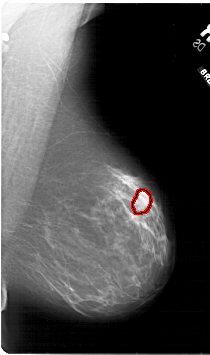

A_1813_1.LEFT_MLO

LEFT_MLO LINES 6016 PIXELS_PER_LINE 4051 BITS_PER_PIXEL 12 RESOLUTION 43.5 NON_OVERLAY

FILE: A_1813_1.RIGHT_MLO.OVERLAY

TOTAL_ABNORMALITIES 1

ABNORMALITY 1

LESION_TYPE MASS SHAPE LOBULATED MARGINS ILL_DEFINED

ASSESSMENT 4

SUBTLETY 3

PATHOLOGY BENIGN

TOTAL_OUTLINES 1

BOUNDARY